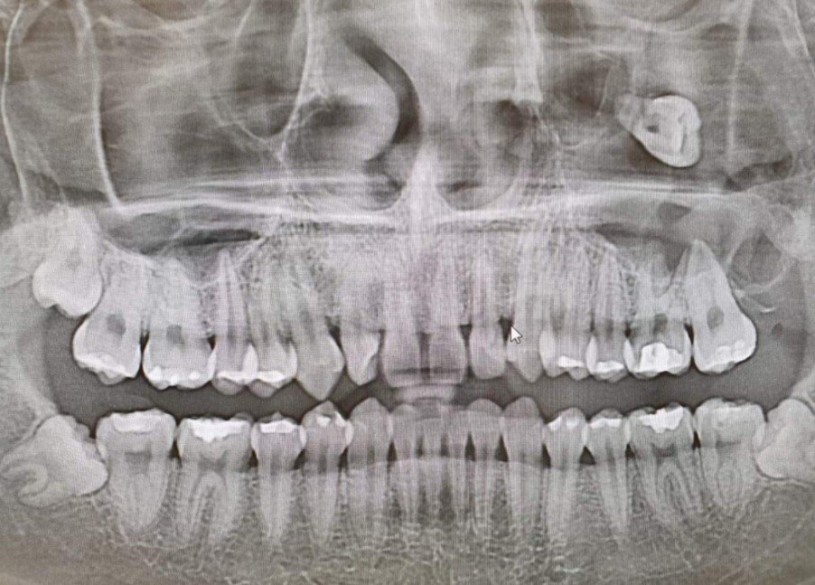

🏥 병원ㅣ질병ㅣ질환/치과 동네병원에선 발치가 힘들다는 사랑니 by 두용이 2022. 2. 4. 반응형 동네병원에선 발치가 힘들다는 사랑니 그러하다 반응형 공유하기 게시글 관리 외시경실 관련글 치아교정은 성형수술이 아니다 (치과) 매복수평쌍사랑니 18세기 사람이 묘사한 충치의 고통.jpg 치과 전화번호 의미 댓글